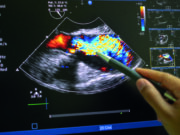

New focus on education needed to improve uptake of intracoronary imaging

Better provision of hands-on education and case-based learning models are among the actions that w...